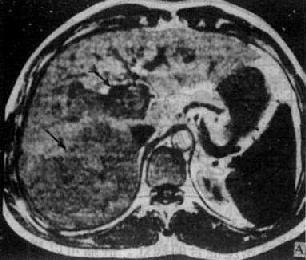

原发性肝癌在T1WI上肝癌的信号强度低于肝,境界常不清楚,有时难以认出。在T2WI上癌瘤较易识别,其信号高于正常肝,常不均匀。癌瘤中心常有不规则更低信号区,肿瘤边缘有时有一低信号的包膜(图4-3-6)。注射造影剂后肝癌信号明显增强,可低于或高于正常肝的信号,境界更为清楚,其中低信号区(出血、坏死、瘢痕)则无强化。若有门静脉内瘤栓,可于低信号的门静脉中出现高信号块影。

图4-3-6 肝癌(MRI)

A、T1WI肝右叶可见大块较低信号区,其内信号不均,轮廓不规

则(↓)。门静脉内可见相同信号强度影像,为癌栓所致(↓)

B、T2WI上述稍低信号区成为稍高信号区(↓),门静脉内癌栓的信

号也增强(↓)